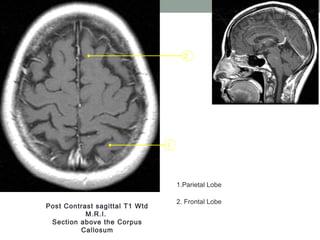

Post Contrast sagittal T1 Wtd

M.R.I.

Section above the Corpus

Callosum

1.Parietal Lobe

2. Frontal Lobe

1 2 Post Contrast sagittalT1 Wtd M.R.I. Section above the Corpus Callosum 1.Parietal Lobe 2. Frontal Lobe